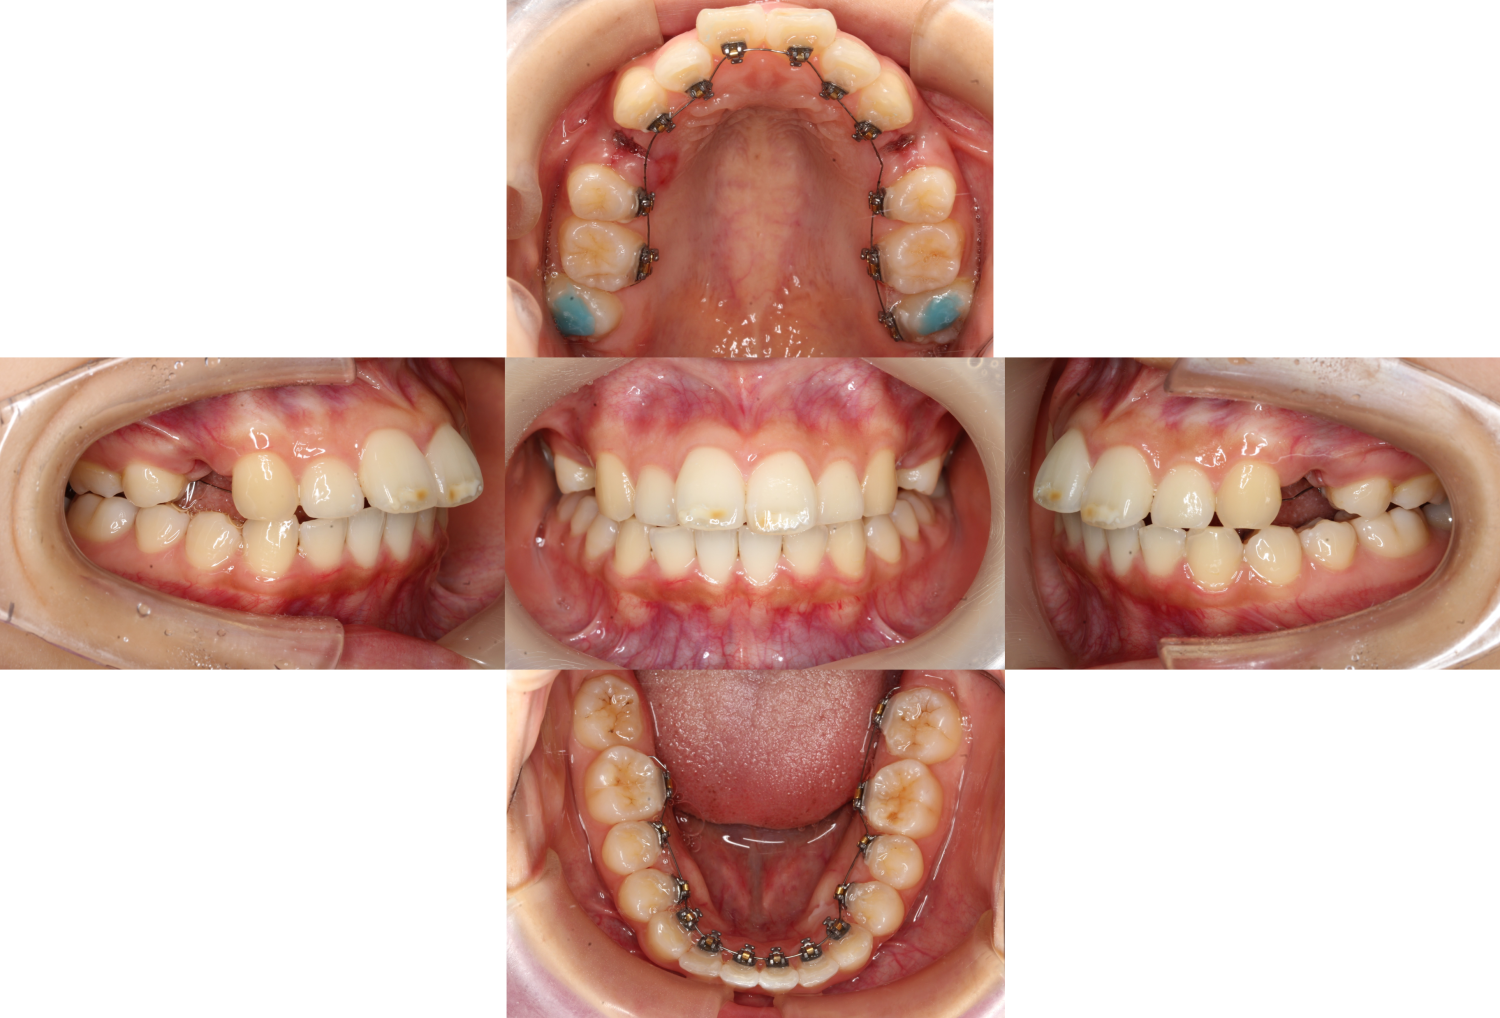

抜歯後装置を装着しました

下の歯は一見キレイに並んでいるように見えますが、

見た目だけでなくしっかりと噛める治療を施すため

上の歯や顎に合わせて細かいガタツキや、歯の高さ、角度などを調整します。